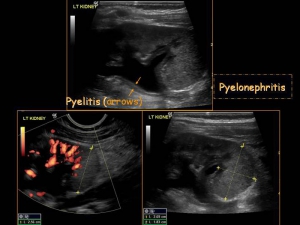

Ακτινολογικά ευρήματα:

-Βλάβες τριγωνικές,σαν σφήνα ή στρογγύλες,με εστιακή διόγκωση και υποαιμάτωση του παρεγχύματος.

-Στον υπερηχοτομογραφικό έλεγχο παρατηρούνται περιοχές παθολογικής ηχοδομής,οι οποίες δεν εμφανίζουν χρώμα μετά την έγχρωμη Doppler υπερηχοτομογραφία.